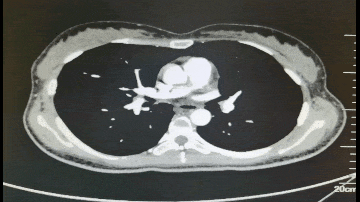

2021年7月8日 腹部CT

◈ 2021年7月8日,患者为求手术治疗就诊于我院门诊,行腹部CT检查提示:盆腔见不规则低密度影,包绕膀胱及子宫,与双侧附件及邻近肠管、右侧髂血管分界不清,三期CT值约为28Hu、27Hu、34Hu,其内密度不均,可见片状高密度影及钙化密度影。检查诊断:盆腔占位病变,考虑粘液瘤可能性大,建议进一步检查(因放射科无法获得胃肠间质瘤诊断及治疗病史)。结合患者病史及腹部CT结果,目前患者肿瘤包绕膀胱及子宫,与双侧附件分界不清。术中可能需要切除附件,因患者为年轻未婚未育女性,且直接手术的临床价值尚不明确,暂不考虑手术治疗。建议继续给予口服伊马替尼400mg QD。